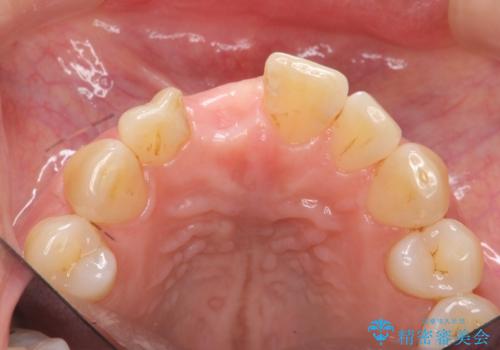

- 前歯を外傷により失い、審美性の改善を求めて来院されました。

横の歯を削る必要のあるブリッジ治療、着脱の必要な入れ歯に強い抵抗があったためインプラント治療を計画します。

前歯のインプラントを審美的に仕上げるには、インプラント周囲に十分な骨の量と厚みのある歯肉、そして埋入位置の精密な位置付けが重要です。